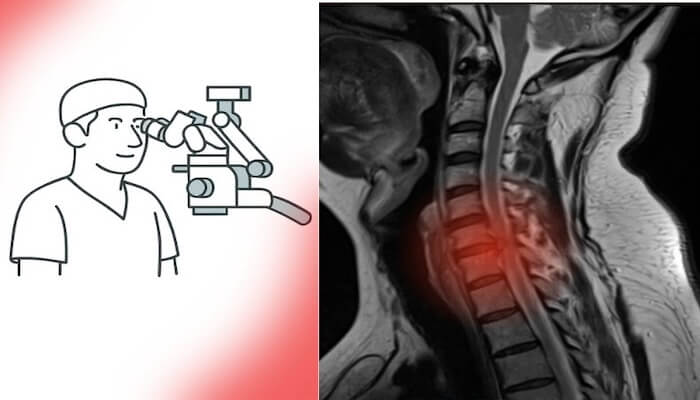

Günümüzde MR ve BT gibi ileri radyolojik görüntüleme yöntemlerine erişim son derece kolaylaştı. Artık neredeyse her şehirde donanımlı hastaneler ve modern tanı merkezleri bulunuyor. Bu sayede en küçük lezyonlar bile erken dönemde saptanabiliyor.

Türkiye’de sağlık hizmetlerine erişim ve radyolojik altyapı son yıllarda ciddi bir ivme kazandı; adeta sağlıkta zirveye ulaşıldı.Bu gelişmeler, tanı sürecini hızlandırarak hem beyin tümörü ameliyatı hem de omurga cerrahisi gerektiren hastaların erken dönemde tespit edilmesini sağladı. Eskiden geç tanı alan birçok vaka, artık uygun zamanda cerrahi müdahaleye yönlendiriliyor. Böylece erken tanı, hem nörolojik kayıpların önlenmesine hem de cerrahi başarı oranlarının artmasına katkı sunuyor.

Beyin ve omurga cerrahisinde son yıllarda yaşanan teknolojik ilerlemeler, cerrahiye bakış açısını tamamen değiştirdi. Artık ameliyatlar daha küçük kesilerle, daha az kan kaybıyla ve çok daha kısa iyileşme süreleriyle gerçekleştirilebiliyor.

Mikrocerrahi, endoskopik cerrahi ve nöronavigasyon sistemleri sayesinde sinir dokuları korunarak işlem yapılabiliyor. Bu da hem cerrahi güvenliği artırıyor hem de genç hastaların ameliyat kararını kolaylaştırıyor.

Eskiden korkulan “uzun iyileşme süresi” veya “kalıcı hasar riski” gibi endişeler, yerini yüksek başarı oranlarına ve hızlı dönüş sürecine bıraktı. Özellikle bel fıtığı ameliyatı, boyun fıtığı ameliyatı ve beyin tümörü ameliyatı gibi operasyonlar artık minimal invaziv yöntemlerle çok daha kısa sürede tamamlanabiliyor.

Ameliyat mikroskopları, nöronavigasyon sistemleri, intraoperatif monitörizasyon ve endoskopik teknikler sayesinde cerrahlar artık milimetrik düzeyde güvenle çalışabiliyor. Bu da komplikasyon riskini belirgin biçimde azalttı.

Son yıllarda beyin ve omurga cerrahisinde yaşanan teknolojik devrim, ameliyatların güvenliğini ve başarısını belirgin biçimde artırdı. Mikrocerrahi, endoskopik ve minimal invaziv yaklaşımlar sayesinde artık çok daha küçük kesilerle, minimal kan kaybı ve kısa iyileşme süresiyle operasyonlar yapılabiliyor.